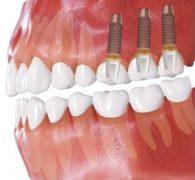

Brak górnych trzonowców

Brak górnych trzonowców (brak skrzydłowy). Dostateczny wymiar pionowy kości umożliwia implantację. W takim przypadku jedyną alternatywą dla implantów jest ruchoma proteza - wykonanie mostu jest niemożliwe.